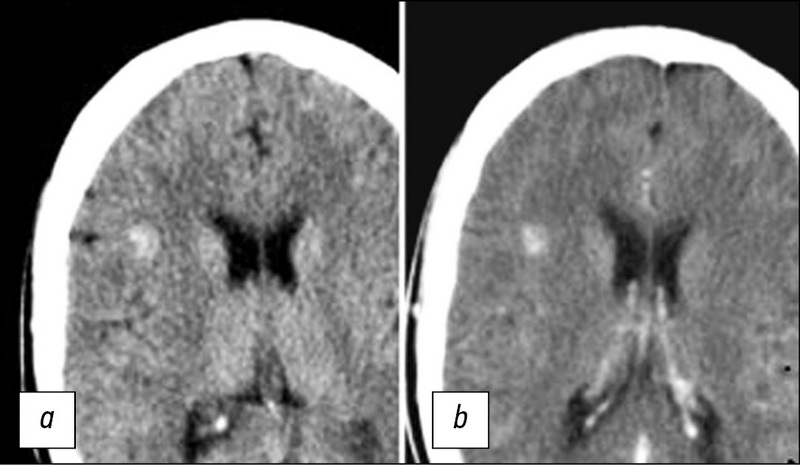

MRI evaluation of the neoadjuvant chemoradiation therapy result in a patient with rectal cancer, supplemented with T2-WI texture analysis of the tumor: a clinical case

The article presents a clinical case of using the active follow-up strategy (the so-called watch & wait) in a 73-year-old patient with cancer of the lower rectum with a good response to neoadjuvant chemoradiation therapy (NCRT). After 3 years of regular follow-up, including digital rectal examination, rectoscopy and MRI, indicating the absence of tumor progression, PET/ CT with 18F-FDG was obtained, which revealed a region of hypermetabolic activity in the lower rectum (SUVmax 27.1), in connection with which it was decided to carry out surgical treatment. When discussing the issue of the volume of the operation, MRI data were taken into account, supplemented by the results of T2-weighted texture analysis, which confirmed the absence of progression. The patient underwent organ-preserving treatment in the amount of transanal tumor resection. Pathomorphological examination after surgery established the inflammatory changes in the intestinal wall and absence of tumor. This case demonstrates the effectiveness of the standard examination volume when using the watch & wait strategy and the possibility of using T2-WI texture analysis to increase the reliability of MRI assessment of tumor response to chemotherapy.